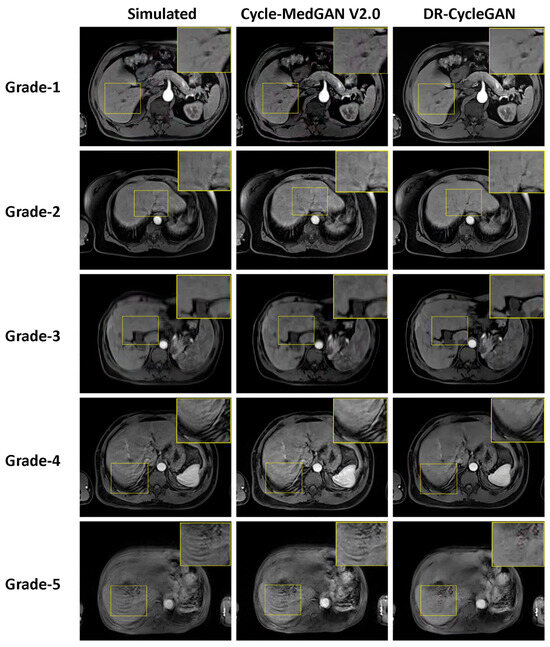

3.2. Evaluation of Unpaired Test Dataset

| Total (n = 474 examinations) | |

| Before correction | 2.9 ± 1.3 * |

| DR-CycleGAN | 2.0 ± 0.6 * |

| Cycle-MedGAN V2.0 | 2.4 ± 0.9 * |

| Motion artifact grade-1 (n = 60 examinations) | |

| DR-CycleGAN | 1.0 ± 0.0 |

| Cycle-MedGAN V2.0 | 1.0 ± 0.0 |

| Motion artifact grade-2 (n = 157 examinations) | |

| DR-CycleGAN | 1.9 ± 0.3 |

| Cycle-MedGAN V2.0 | 2.0 ± 0.4 |

| Motion artifact grade-3 (n = 110 examinations) | |

| DR-CycleGAN | 2.1 ± 0.5 # |

| Cycle-MedGAN V2.0 | 2.4 ± 0.6 |

| Motion artifact grade-4 (n = 78 examinations) | |

| DR-CycleGAN | 2.4 ± 0.5 # |

| Cycle-MedGAN V2.0 | 3.0 ± 0.7 |

| Motion artifact grade-5 (n = 69 examinations) | |

| DR-CycleGAN | 2.7 ± 0.6 # |

| Cycle-MedGAN V2.0 | 3.8 ± 0.7 |